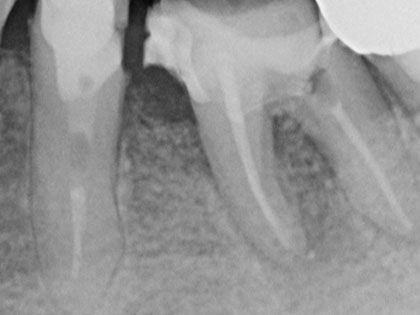

根管治療 症例紹介

根管治療症例

感染根管治療を行った症例

前歯が腫れているとの事で来院され、感染根管治を行った患者様の症例になります